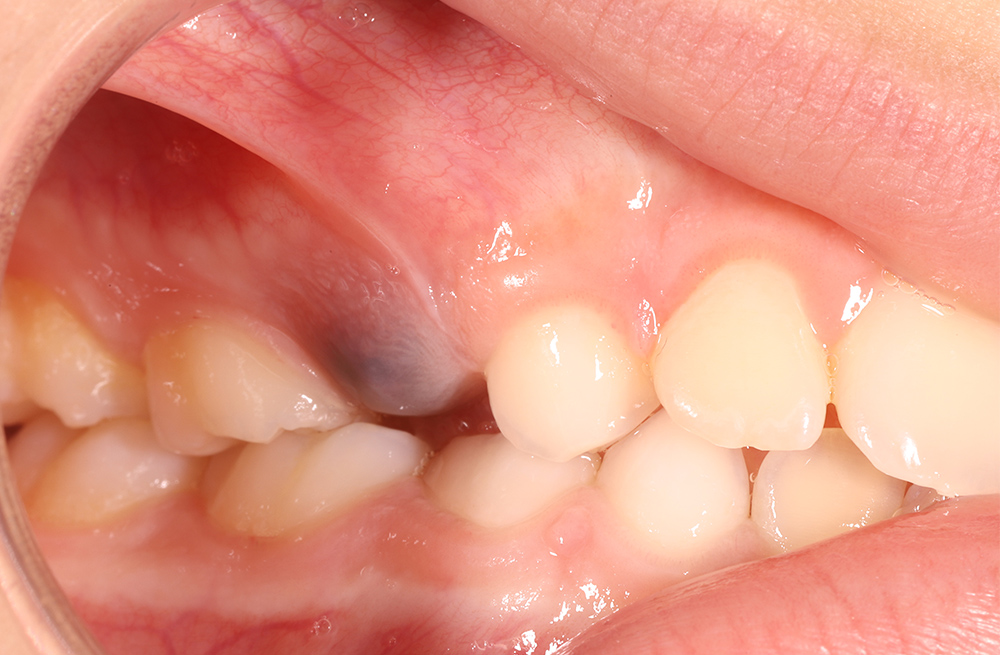

Гематома на десне при прорезывании зуба у ребенка